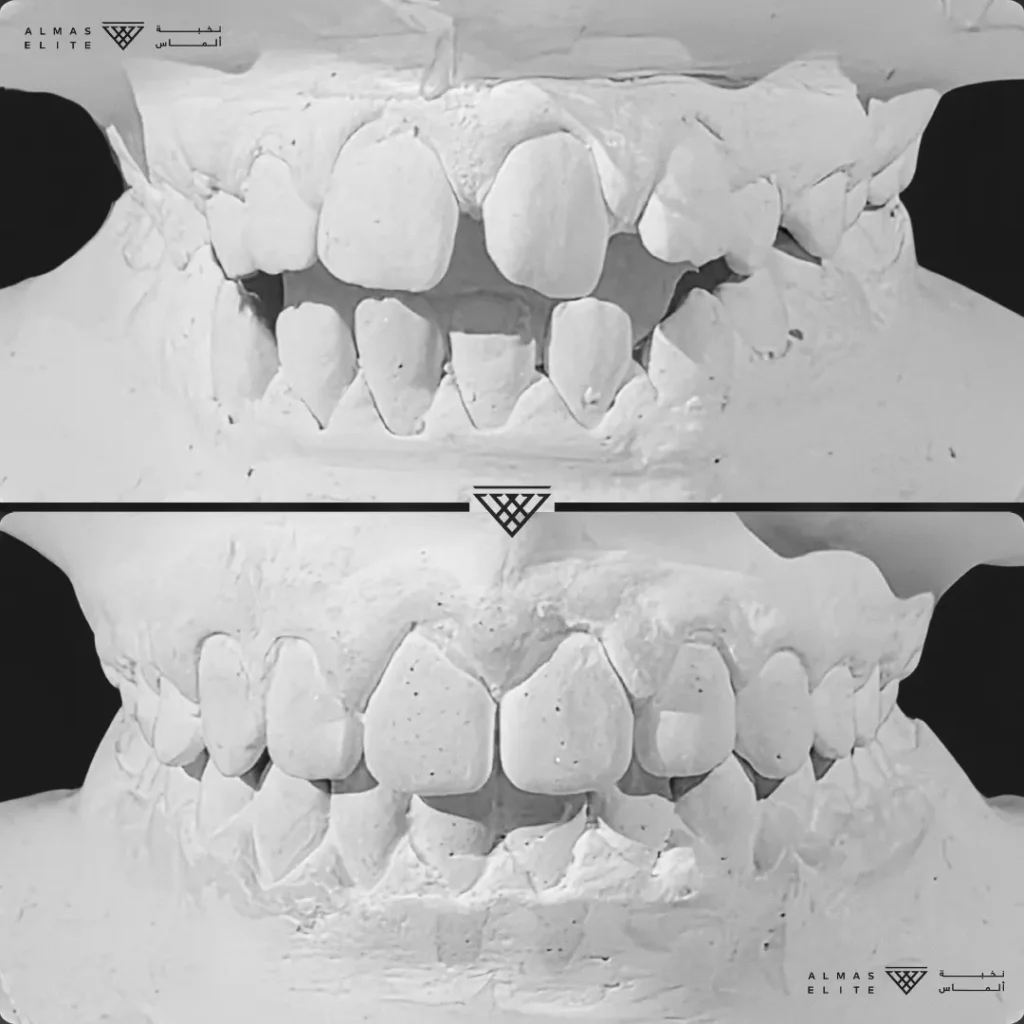

- تشخيص دقيق يشمل الأشعة والتحليل الرقمي للأسنان والفكين.

٢) التقييم والتشخيص الشامل

يشمل صور الأشعة والتحليل الرقمي للأسنان والفكين للوصول إلى تشخيص دقيق.